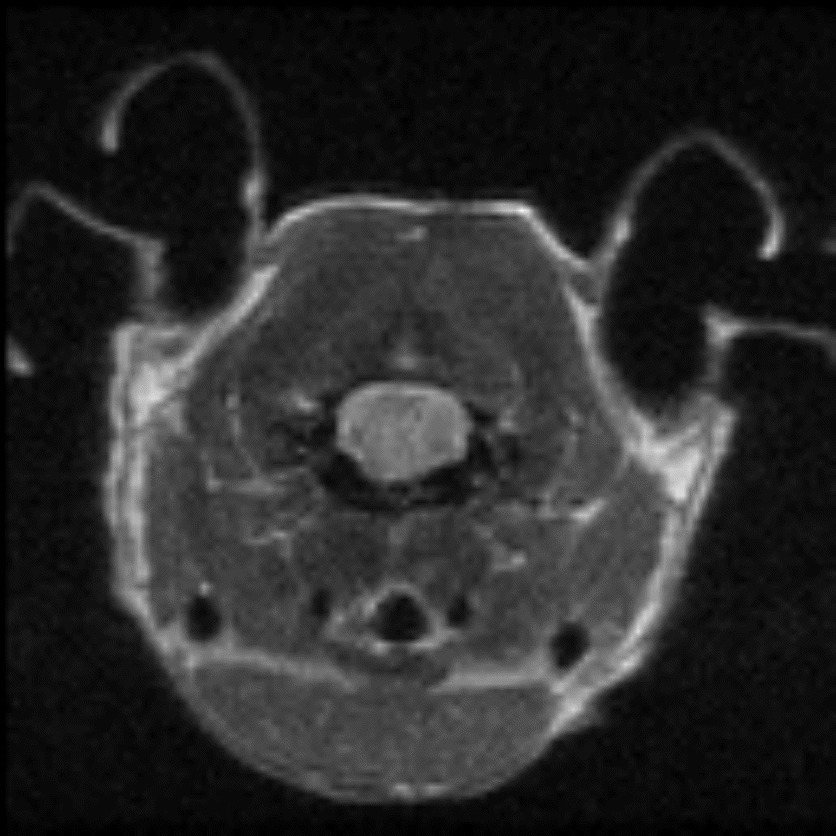

Hindlimb tumor growth: Monitoring the growth of xenograft tumor grown in the mouse hindlimb is identified with T2-weighted images. Segmentation of tumor region of interests (in red) on each tumor-containing slice allows accurate volume quantification. Image Credit: Scintica Instrumentation Inc

Monitoring the growth of xenograft tumor grown in the mouse hindlimb is identified with T2-weighted images. Segmentation of tumor region of interests (in red) on each tumor-containing slice allows accurate volume quantification. Image Credit: Scintica Instrumentation Inc